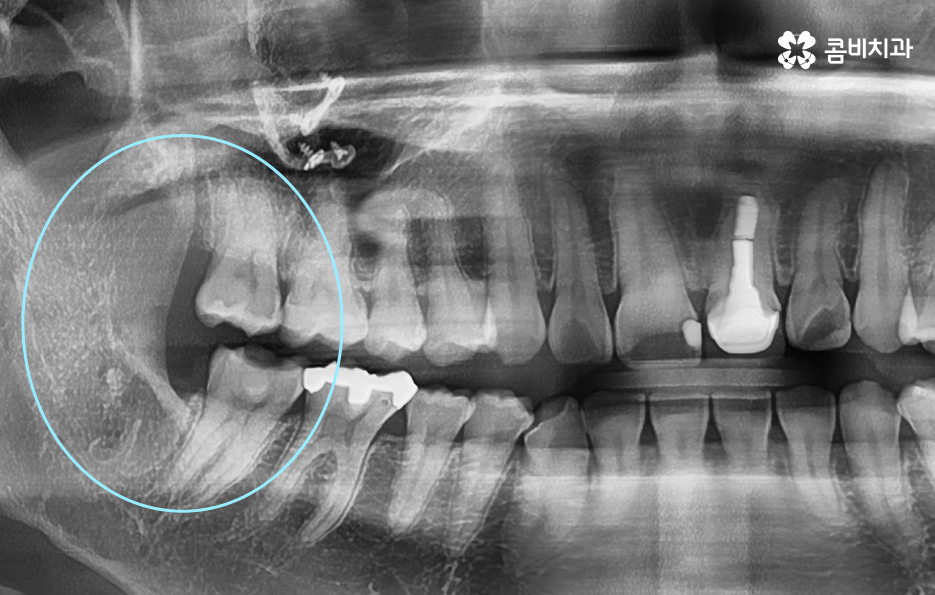

현대인들은 사랑니의 위치가 좋지 않아서 주변 치아와 잇몸에 염증이 발생되는 사례가 많고 특히 하악에 매복 사랑니가 있는 경우가 많은데 완전히 누워서 자라는 사랑니는 발치 자체도 어렵지만 뿌리가 깊어지기 전에 발치하는 것이 발치나 회복에도 수월하기 때문에 정확한 사랑니 발치 시기의 골든타임을 놓치지 않기 위해서도 사랑니가 나올 무렵에 자신의 사랑니가 어떻게 자라고 있는지 확인하실 필요가 있어요